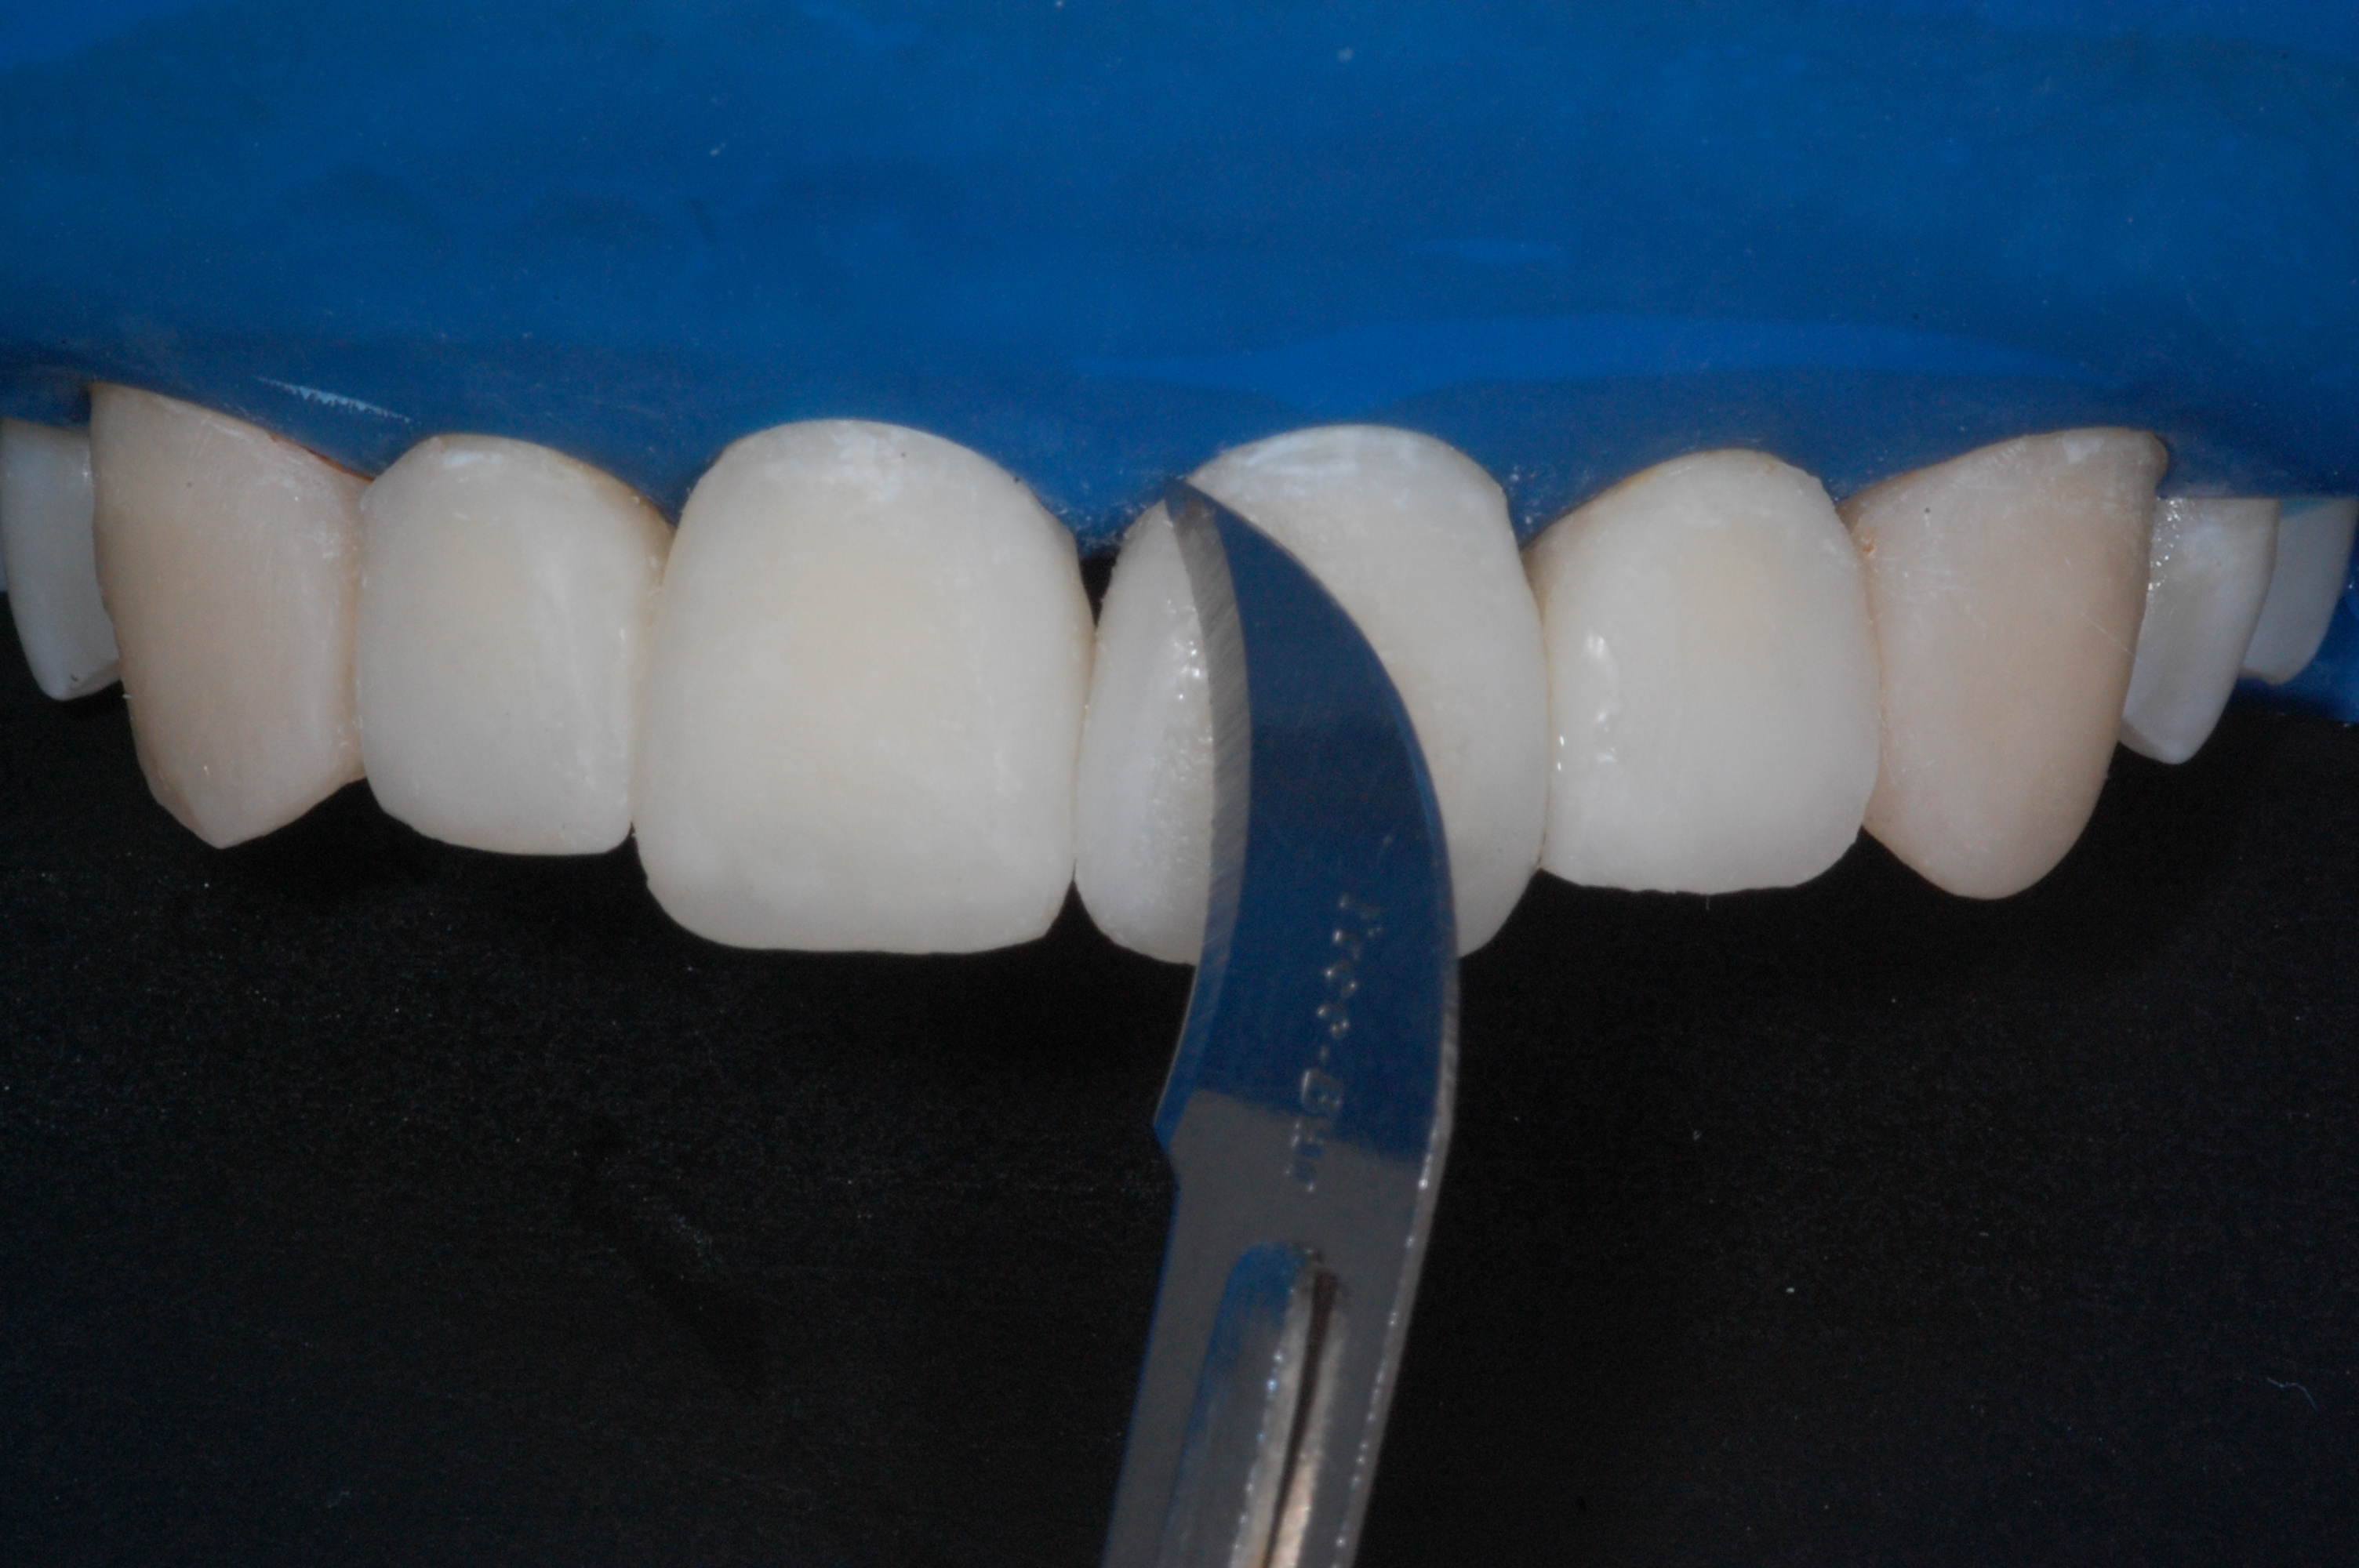

The presence of diastema, between anterior teeth, distorts a pleasing smile by concentrating the observer’s attention on the spaces. The patient’s needs and expectations must be considered in the process of treatment planning to ensure satisfaction with the treatment outcomes. There are many forms of therapy that can be used for diastema closure. A carefully developed diagnosis, which includes a determination of the causal elements and advanced treatment planning, allows the most appropriate treatment to be selected for each case. The aim of this paper is present a multidisciplinary approach as a solution to multiple diastemas in the anterior region using gingival tissue recontouring and direct adhesive restorations, with minimum wear of the dental structure, after the orthodontic intervention discussing the minimal intervention to obtain imperceptive and aesthetic final restoration. Thirty-six months after the treatment was carried out, the final aesthetic was maintained with all dental element details and gingival tissue harmony, without recurrence of periodontal pockets and the preservation of the tooth color and shape.